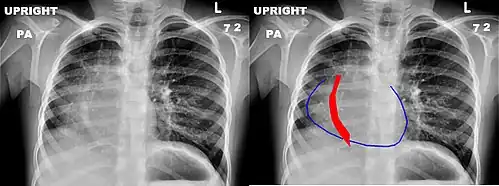

Scimitar syndrome, or congenital pulmonary venolobar syndrome, is a rare congenital heart defect characterized by anomalous venous return from the right lung (to the systemic venous drainage, rather than directly to the left atrium).[1] This anomalous pulmonary venous return can be either partial (PAPVR) or total (TAPVR). The syndrome associated with PAPVR is more commonly known as Scimitar syndrome after the curvilinear pattern created on a chest radiograph by the pulmonary veins that drain to the inferior vena cava.[2] This radiographic density often has the shape of a scimitar, a type of curved sword.[2] The syndrome was first described by Catherine Neill in 1960.[3]

The anomalous venous return forms a curved shadow on chest x-ray such that it resembles a scimitar. This is called the Scimitar Sign. Associated abnormalities include right lung hypoplasia with associated dextroposition of the heart, pulmonary artery hypoplasia and pulmonary sequestration. Incidence is around 1 per 100,000 births.[4]